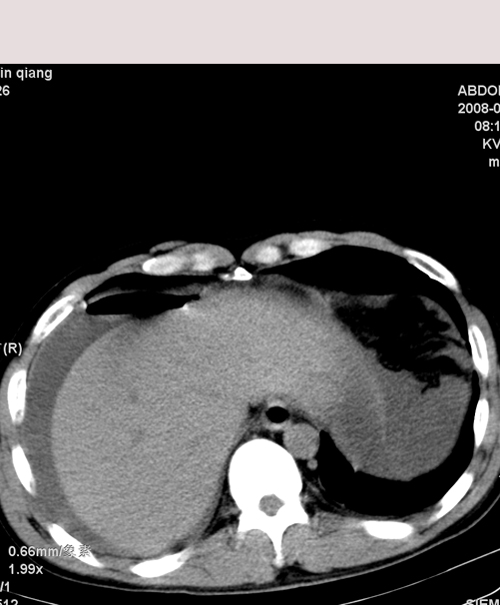

以下是引用muzi888在2008-7-15 10:45:00的发言:[br]大量腹腔积液,气腹,肾皮质弧形高密度影,诊断;1 空腔脏器穿孔 2 右肾包膜下血肿

以下是引用随光逐影在2008-7-15 11:18:00的发言:[br]考虑为:1)腹部空腔脏器穿孔。2)右肾破裂并肾包膜下血肿,肾盂积血。3)腹水(血)。